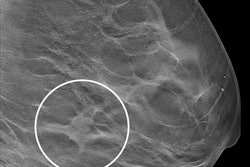

Radiologists have studied and continue to research how breast density plays into breast cancer risk. Previous studies have demonstrated that dense breast tissue masks breast cancers on mammography, and that supplemental imaging such as ultrasound and MRI confirms suspicious findings within dense tissue.

However, advocates for breast density notification say that such messaging impacts many women. Wendie Berg, MD, PhD, from the University of Pittsburgh Medical Center and Magee-Womens Hospital said that for the 40% of women who have dense breasts, cancers are more likely to develop and are more likely not to be seen on the mammogram.

"This allows for individualized, risk-based screening decisions to be made by the patient and her healthcare team," she said." Numerous studies have demonstrated that screening ultrasound in women with dense breasts can detect breast cancers that were missed on the mammogram."